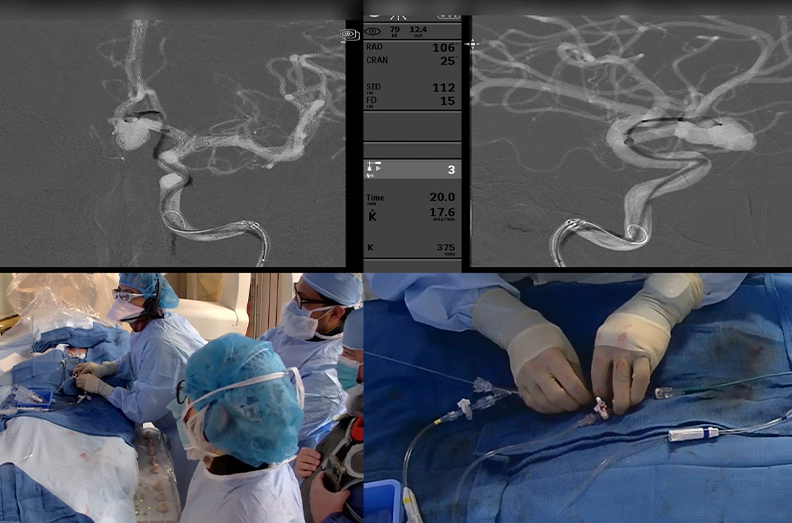

Dr. Mehta, a vascular and interventional neurologist and medical director of the Comprehensive Stroke and Neurointerventional Surgery programs at the Memorial Neuroscience Institute, performed the first live-streamed endovascular neurosurgery to fully secure a complex brain aneurysm using the novel Microvention Woven EndoBridge (WEB) device. Dr. Delgado, a neurointerventional radiologist at Abbott Northwestern Hospital in Minneapolis, logged on through the Proximie virtual operating room to provide technical guidance.

Drs. Mehta and Delgado utilized a minimally-invasive, endovascular treatment on Stephane Desjardins to treat the brain aneurysm, one that had a high probability of being fatal if it had ruptured and bled in the brain. The catheter-based image navigation procedure enabled the placement of the WEB device to secure the aneurysm. The procedure was a success due to the real-time virtual proctoring made possible with the Proximie system.